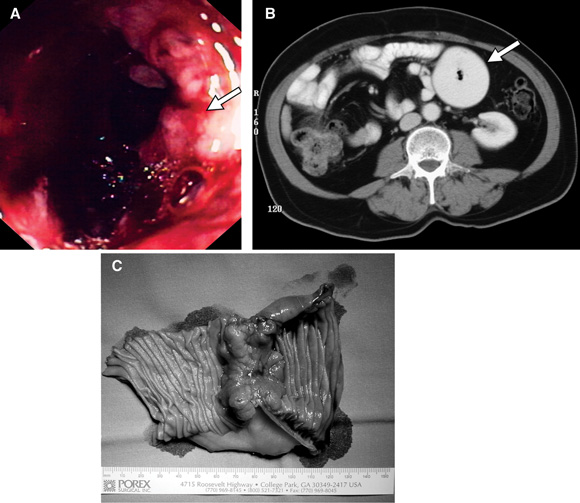

Push enteroscopy revealed an ulcerated adenocarcinoma in the proximal jejunum (A).

Upper gastrointestinal endoscopy showed severe reflux oesophagitis. The first and second parts of the duodenum were normal. Abdominal CT showed a circumferential mass in the proximal jejunum with dilation of proximal bowel (B). Small bowel follow-through then showed an annular, stenosing lesion in the region of the duodenojejunal flexure.

At laparotomy, a localised adenocarcinoma was resected (C). The patient had adjuvant chemotherapy and 12 months after surgery was asymptomatic, taking no medication, and had no evidence of recurrence.

A: Small bowel carcinoma detected on push enteroscopy (Patient 1). B: Abdominal CT scan showing a large dilated small bowel loop in the left upper quadrant (Patient 2). C: Operative specimen showing a localised, constricting cancer (Patient 2).